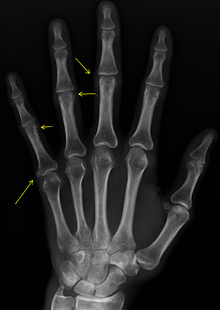

CREST causes thickening and tightening of the skin with deposition of calcific nodules ("calcinosis").

Though it is the most easily recognizable manifestation, it is not prominent in all patients. Thickening generally only involves the skin of the fingers distal to the metacarpophalangeal joints in CREST. Early in the course of the disease, the skin may appear edematous and inflamed. Eventually, dermal fibroblasts overproduce extracellular matrix leading to increased tissue collagen deposition in the skin. Collagen cross-linking then causes a progressive skin tightening. Digital ischemic ulcers commonly form on the distal fingers in 30-50% of patients.[2]